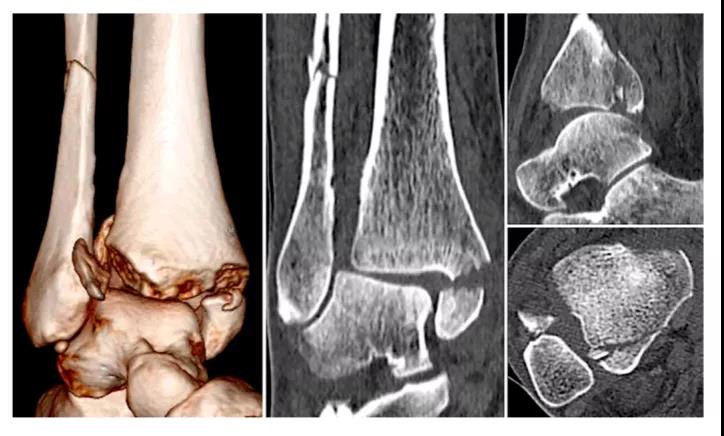

① 四踝骨折示意图:1.内踝;2.外踝;3.后踝;4.胫骨前结节(前踝)。

② 四踝骨折典型病例图。